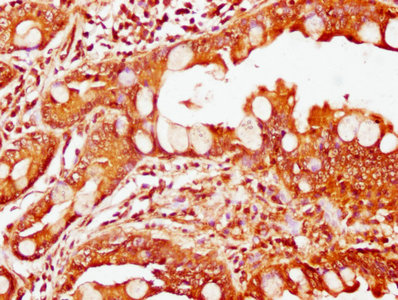

IHC image of CSB-PA882156LA01HU diluted at 1:200 and staining in paraffin-embedded human colon cancer performed on a Leica BondTM system. After dewaxing and hydration, antigen retrieval was mediated by high pressure in a citrate buffer (pH 6.0). Section was blocked with 10% normal goat serum 30min at RT. Then primary antibody (1% BSA) was incubated at 4°C overnight. The primary is detected by a biotinylated secondary antibody and visualized using an HRP conjugated SP system.